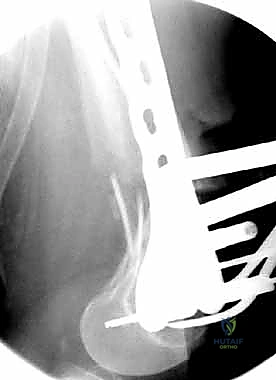

المرحلة الرابعة: التثبيت النهائي بالشرائح والمسامير (Fixation)

يتم استخدام "شرائح الإغلاق التشريحية" (Anatomical Locking Plates) المصنوعة من التيتانيوم عالي الجودة. هذه الشرائح مصممة خصيصاً لتأخذ شكل الجزء السفلي من عظم الفخذ. يتم تمرير الشريحة أسفل العضلات وتثبيتها بمسامير تغلق داخل الشريحة نفسها (Locking Screws)، مما يوفر ثباتاً ميكانيكياً هائلاً، حتى في حالات العظام الهشة.

في بعض الحالات المعقدة جداً، قد يتطلب الأمر استخدام شريحتين (Dual Plating) لضمان عدم تحرك الكسر أثناء فترة التعافي.

المرحلة الخامسة: الإغلاق التجميلي

بعد التأكد التام من استقرار الكسر وحركة المفصل عن طريق الأشعة داخل غرفة العمليات، يتم إغلاق الجرح بطبقات متعددة باستخدام خيوط تجميلية لتقليل الندبات، ووضع أنبوب تصريف (Drain) لمنع تجمع الدم.